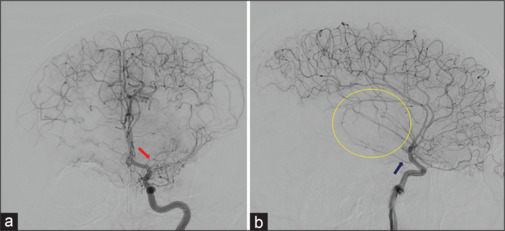

烟雾病(MMD)是一种以颅内动脉进行性闭塞为特征的脑血管疾病,常导致脑卒中和脑出血。虽然烟雾病通常影响颅内血管系统,但我们报告了一个不寻常的双侧椎体狭窄闭塞病例,导致37岁烟雾病患者椎基底动脉功能不全,并通过血管成形术和椎动脉支架置入术治疗。回顾文献显示椎动脉近端受累是烟雾病的罕见表现。该报告有助于了解烟雾病的临床谱,并强调需要警惕和意识到受影响个体颅内外血管并发症的可能性。

Moyamoya disease (MMD) is a cerebrovascular disorder characterized by progressive occlusion of intracranial arteries, often leading to stroke and intracerebral hemorrhage. While MMD classically affects the intracranial vasculature, we present an unusual case of bilateral vertebral steno-occlusion, resulting in vertebrobasilar insufficiency in a 37-year-old man with MMD and treated with angioplasty and stenting of the dominant vertebral artery. Review of the literature demonstrates proximal vertebral artery involvement to be a rare manifestation of moyamoya disease. This report contributes to the understanding of the clinical spectrum of MMD and emphasizes the need for vigilance and awareness of the possibility of extracranial vascular complications in affected individuals.